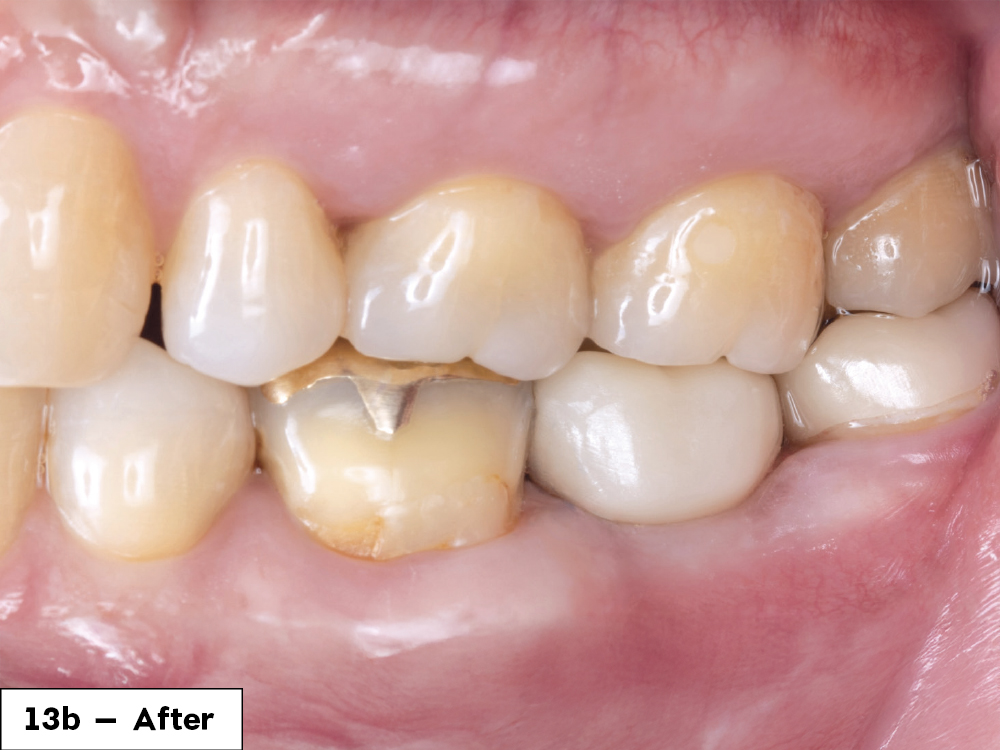

Before tooth surgery

1 year after tooth surgery

Figures 13a, 13b: One year after removing the tooth and infection, the final screw-retained crown demonstrated great stability and esthetics. The patient was happy with the restored functionality of his tooth.